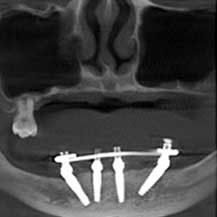

深圳正夫口腔穿颧种植牙真人实例对比分享